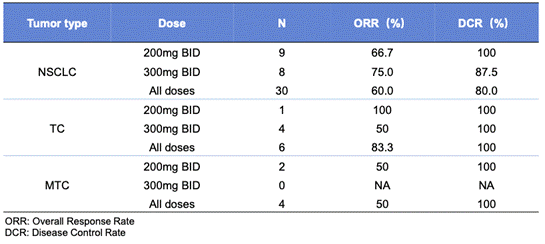

еңЁ40дҫӢеҸҜиҜ„дј°зҡ„жӮЈиҖ…дёӯ�пјҢпјҢпјҢпјҢ�пјҢ�пјҢиҮӘеҠӣе®ЎжҹҘ委е‘ҳдјҡеҮӯиҜҒRECIST v1.1зЎ®и®Өзҡ„жҖ»зј“и§ЈзҺҮпјҲORRпјүе’Ңз–ҫз—…жҺ§еҲ¶зҺҮпјҲDCRпјүеҲ’еҲҶдёә62.5%е’Ң85%�гҖӮгҖӮгҖӮгҖӮ�гҖӮе…¶дёӯ�пјҢпјҢпјҢпјҢ�пјҢ�пјҢRETиһҚеҗҲNSCLCпјҲn=30пјүгҖҒTCжӮЈиҖ…пјҲn=6пјүгҖҒMTCжӮЈиҖ…пјҲn=4пјүзҡ„ORR/DCRеҲ’еҲҶдёә60%/80%гҖҒ83.3%/100%е’Ң50%/100�гҖӮгҖӮгҖӮгҖӮ�гҖӮиҖҢIRCеңЁ 200mgе’Ң 300mgпјҲBIDпјүзҡ„еүӮйҮҸз»„дёӯжүҖжөӢе®ҡзҡ„ORRе’ҢDCRеҲ’еҲҶдёә 66.7%/100% е’Ң 75%/91.7%[1]�гҖӮгҖӮгҖӮгҖӮ�гҖӮ

иЎЁ2.ORRгҖҒDCRж•Ҳжһң